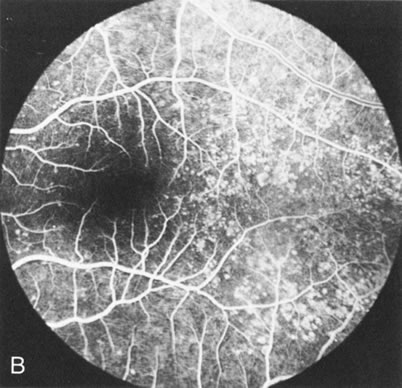

In retinitis pigmentosa (RP), the pigment abnormalities of atrophy, migration, and clumping are made apparent by transmitted hyperfluorescence and blocked hypofluorescence (Fig. 1A). Patients who have very minimal pigmentary alterations (pauci pigmentary RP) or no pigment abnormalities (RP sine pigmento) may show the abnormalities on fluorescien angiography (FA). It is uncommon to see choriocapillaris atrophy except in the late stages. This finding corresponds to the histopathology, which shows that the earliest abnormalities are in the photoreceptors and that the choroid is normal.1

Fig. 1. Retinitis pigmentosa. A. A typical area of bone spicule pigmentation. B. Diffuse dye leakage is apparent throughout the posterior pole. C. The early angiogram shows dilated and irregular retinal radial peripapillary capillaries and perifoveal retinal capillaries. D. Leakage from these vessels are evident in the late angiogram.

Dye leakage in RP may occur from the retinal vessels or at the level of the retinal pigment epithelium (Fig. 1B).2–4 The leakage may be seen in the macula and posterior pole, along the vascular arcades in the distribution of the radial peripapillary capillaries, and in the periphery (where an exudative vasculopathy resembling Coats' disease is suggested).

Of more clinical importance is the role of FA in the diagnosis and treatment of cystoid macular edema (CME) (Fig. 1C and D). Stereoscopic FA indicates that the leakage, which may be diffuse or have the typical petaloid stellate appearance of CME, can come from the perifoveal retinal capillaries, from the choroid through the RPE, or from a combination of both sources.4 With the recent suggestion that CME in RP may be successfully treated with acetazolamide,5, 6 FA is thus important to document the diagnosis of CME, establish the origin(s) of leakage, and follow patients during and after therapy.